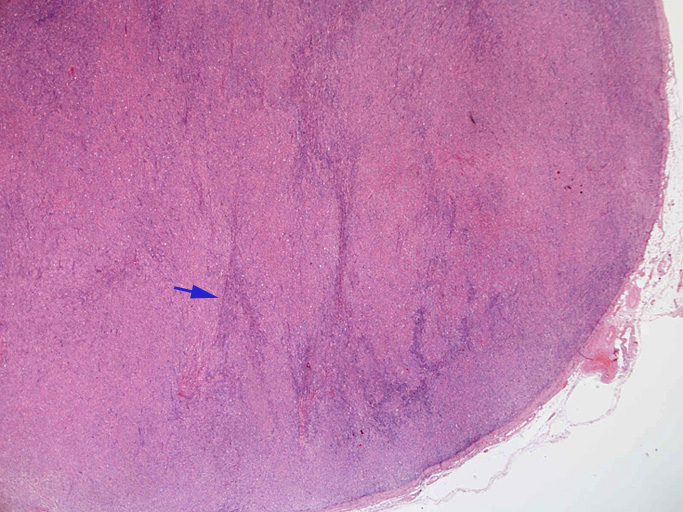

直径17mmの腫大したリンパ節。被膜は軽度線維性肥厚を示す。リンパ節の基本構造は失われ不明瞭な結節様構造が集蔟しているように見える。

光顕および免疫染色所見

結節構造内では, 好酸性細胞質をもつ組織球の増生を背景に大型異型細胞が散在性または集蔟して増殖している。被膜下にも線維化組織内にbizzarreな大型細胞が認められる。リンパ球は小型リンパ球が大型異型細胞を含む組織球性の結節辺縁に存在する。大型細胞は, centroblastic cellが多く, その他 Hodgkin cell-like cell, RS細胞様巨細胞, 腎臓型の核をもった細胞, 多型核の細胞など多彩な形態を示す。異型核分裂像をふくむ核分裂像が多い。